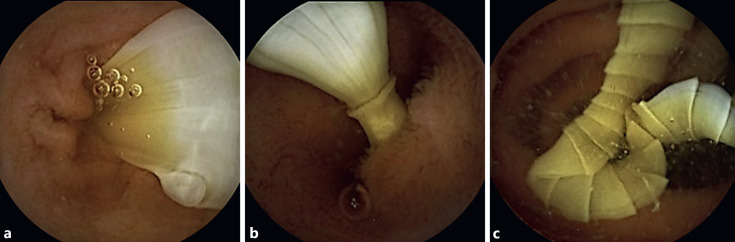

An Unexpected Guest in Capsule Endoscopy: Tapeworm Infection.

胶囊内窥镜的意外之客:绦虫感染。